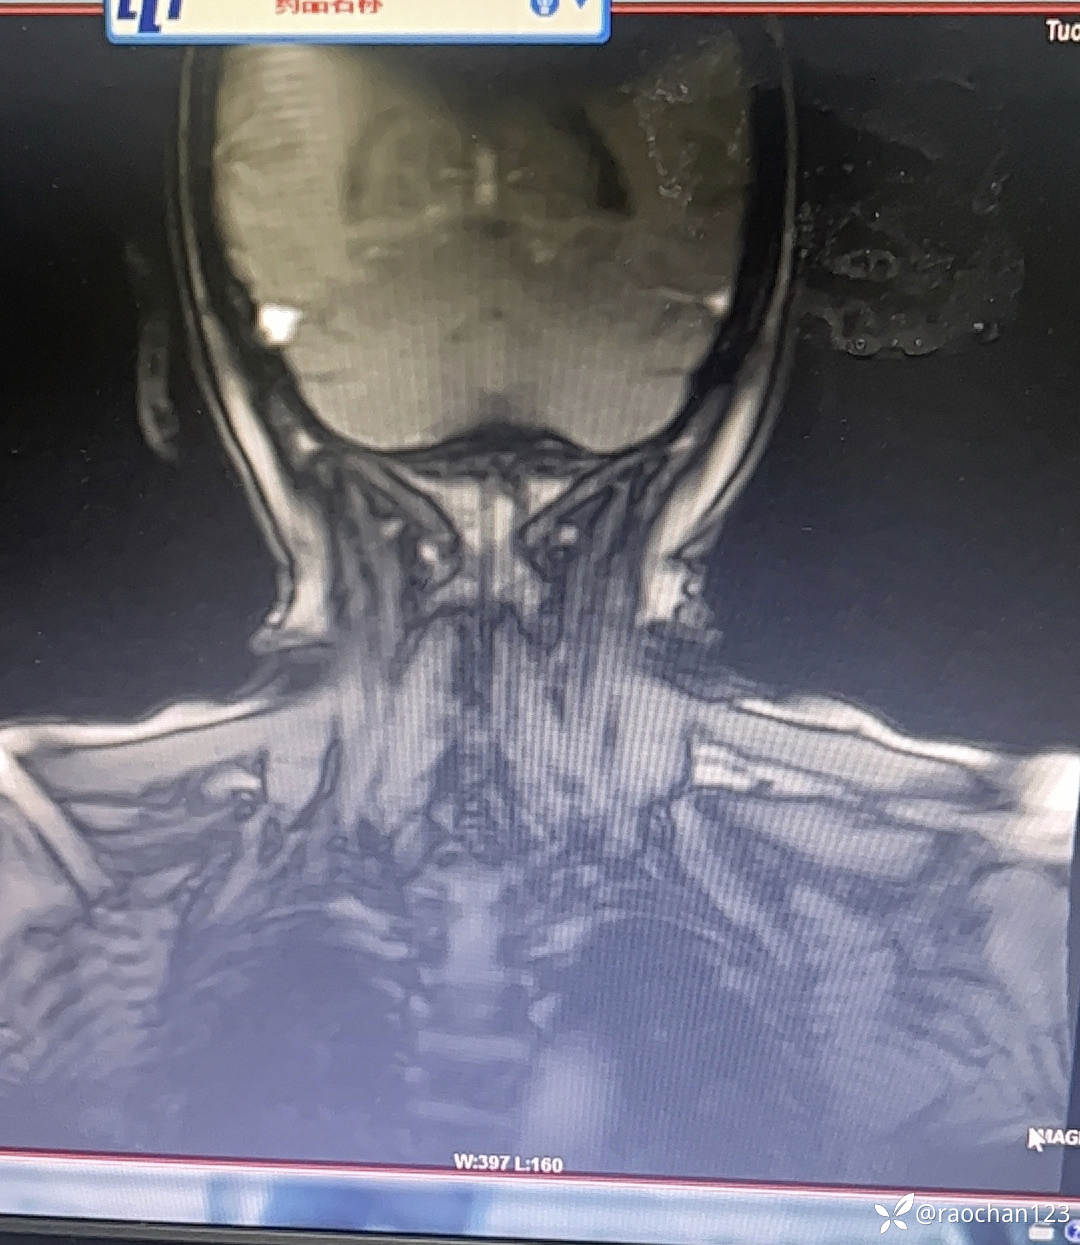

【治疗经过及结果】:给予低流量吸氧,布洛芬混悬液 解热 镇痛,左氧佛沙星抗炎(既往有头孢过敏史)、止痛,热毒宁注射液 清热解毒;艾箱灸、中药塌渍、中药涂擦、火罐、TDP、中药热奄包等中医外治通络祛痛等治疗后,仍有发热,肌酸、肌痛、关节疼痛症状。复查血常规:2024-11-8 13.93# 谷丙转氨酶 45U/L 天门冬氨酸 25U/L 白蛋白 27.0g/L 进一步查乳酸脱氢酶 284U/L 肌酸激酶 26U/L,PCT 0.44ng/ml BNP 811ng/L 免疫五项中IgGA 5.38g/L 血钙 1.94mmol/L 尿微量白蛋白 32.2mg/L 25羟基维生素D 22.68ng/ml 甲胎蛋白、癌胚抗原(-)。颈椎MRI:1.颈椎骨质增生,C4/5、C5/6、C6*7椎间盘轻度突出2、颈后皮下软组织内脂肪堆积,请结合临床。(后颈部皮下软组织内可见异常信号影,T1T2呈高信号,压脂序列呈低信号,颈椎生理曲度变直,椎体后缘连线尚连续,椎体缘骨质光滑,各椎间隙未见狭窄,椎体信号欠均匀,部分椎间盘T2信号减低,C4/5、C5/6、C6/7椎间盘向后轻度突出,硬膜囊轻度受压,椎管无狭窄,黄韧带无肥厚,颈隋未见明显异常)。骨密度:骨质疏松(T值 -4.2)。抗ANA抗体 RF 抗CCP抗体 ENA抗体谱结果待回。患者服用布洛芬混悬液后出现大汗淋漓,血钙偏低,调整为停服布洛芬混悬液、给予醋酸泼尼松10mg 2次/日 口服 解热、抗炎、止痛,金钙尔奇 600mg 2次/日,骨化三醇 0.25ug/日 口服 改善骨质量,暂给予肠内蛋白营养(患者饮食无异常),余治疗同前。